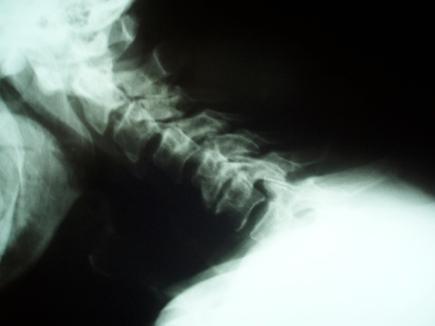

Dialysis-related spondyloarthropathy is a rare cause of spinal deformity and cervical myelopathy. Optimal management of cervical spine spondyloarthropathy often requires circumferential reconstructive surgery, because affected patients typically have both the anterior column and the facet joints compromised. The occasional presence of noncontiguous or "skip lesions" adds an additional level of complexity to surgical management, because decompression and fusion in an isolated segment of neural compression can worsen spine deformity by applying increased stress to adjacent cervical spine segments. We report two cases of hemodialysis patients who presented with cervical myelopathy and initially had anterior cervical discectomy or corpectomy. Because symptoms recurred due to hardware failure, both patients required posterior spine fusion as well. In retrospect, because of the hardware failure, both of these patients might have benefited from a circumferential (combined anterior and posterior) cervical spine reconstruction as their initial treatment.

透析相关性脊柱关节病是脊柱畸形和颈椎脊髓病的罕见病因。颈椎脊柱关节病的最佳治疗通常需要进行环形重建手术,因为受影响的患者通常前柱和小关节均受损。偶尔出现的非连续性或“跳跃性病变”增加了手术治疗的复杂性,因为在孤立的神经受压节段进行减压和融合会因对相邻颈椎节段施加更大压力而加重脊柱畸形。我们报告了两例血液透析患者,他们均表现为颈椎脊髓病,最初接受了颈椎前路椎间盘切除术或椎体次全切除术。由于内固定失败导致症状复发,两名患者均还需要进行后路脊柱融合术。回顾来看,由于内固定失败,这两名患者最初若接受环形(前后联合)颈椎重建术可能会受益。